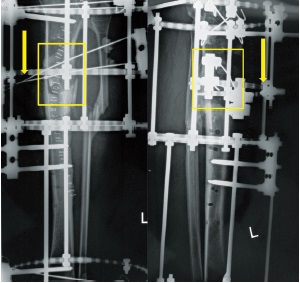

We decided not to open the nonunion site; we applied the Ilizarov apparatus for closed progressive realignment and compression. After 6 months, the fracture was still not healing, pin tracts were infected. So we opted for a surgical revision and resection of a 7 cm long segment of necrotic bone. A distal osteotomy was performed for segmental defect reconstruction with bone transport. At the end of bone transport, X-rays showed a poor contact at the docking site with an anteromedial partial defect of 4.5 cm (Figure 1). We decided to use the technique of fragment transport to deal with this mismatch and increase stability of the docking site. We performed a partial osteotomy of the anterior aspect of the tibia for setting up an anterior fragment to be transported from proximal to distal. The fragment was fixed with two 1.8 mm olive K-wires and connected to a 5/8 ring for progressive bone transport. The frame was removed 5 months later when docking site union was achieved. We observed a gradual bone remodeling during following months (Figure 2). At the last follow-up, four years after frame removal, the patient had a residual equinus deformity of the foot. No recurrence of infections or other complications were observed.

Figure 1. X-ray showing poor contact at the docking site with an anteromedial partial defect

Figure 2. X-ray showing the fragment fixed with two 1.8 mm olive K-wires and connected to a 5/8 ring. Different stages of progressive distraction of the fragment are explained by some sketches. Note regenerate remodeling at 8 months follow-up